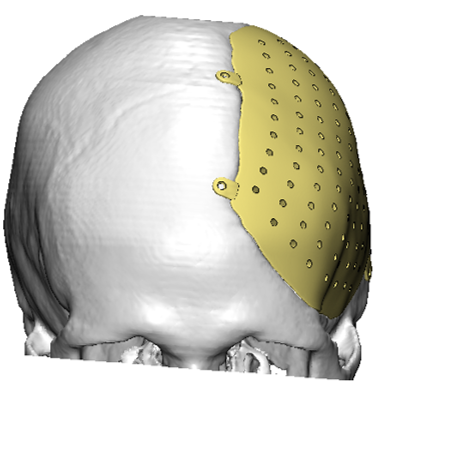

Paciente masculino con un defecto de dimensiones aproximadas de 157.20×109.25mm el cual se reconstruyo con un implante en Peek.